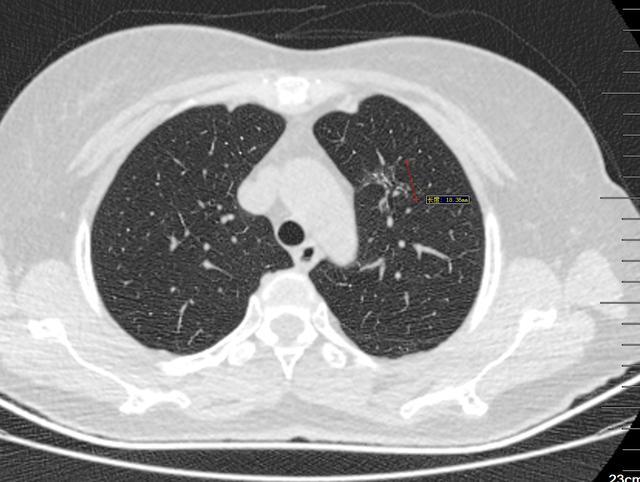

图1、2004年

图2、3 2008年1月10日

图4 2015年4月29日

图5、6 2020年5月15日

漫长的16年,一个纯磨玻璃结节从原位腺癌缓慢正常到浸润性腺癌早期阶段(影像估测),所以说纯磨玻璃结节是不可怕的,可以安心随访,到合适的时机手术完全来得及,不要上来动不动就手术,动不动就消融!